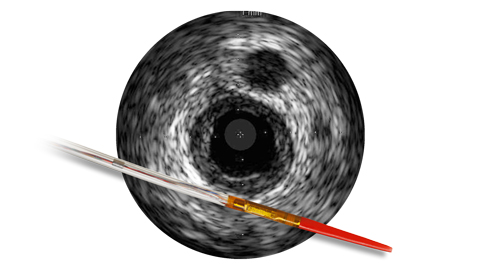

However, with IVUS guidance you can see more clearly and improve patient outcomes with informed pre-stent planning and post-stent optimization.1

IVUS is an AHA/ACC/SCAI Class IIa recommendation for the assessment of angiographically indeterminant left main CAD.9 IVUS may help to determine: • Lesion significance • Vessel sizing • Optimal stent deployment

Using IVUS for long lesions (stents ≥ 28mm) was associated with a 52% reduction in MACE at 1 year in the IVUS-XPL randomized control trial.11 IVUS may help to determine: • Vessel size and length of disease • Positive remodeling • Plaque burden • Stenosis